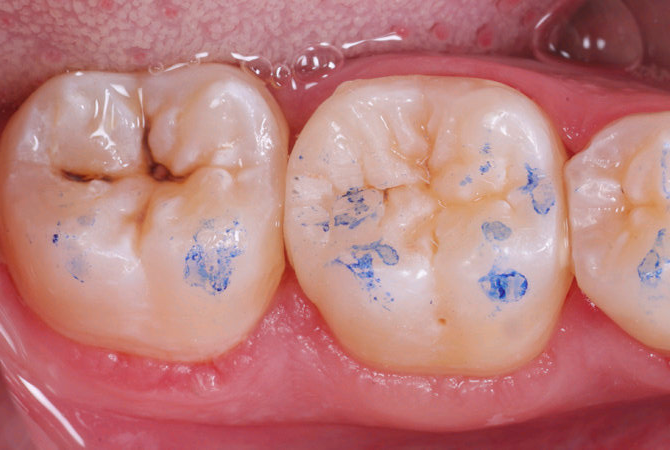

Paziente femmina di 40 anni che si presenta alla nostra attenzione per dolore provocato da stimoli termici ed al dolce a carico del III quadrante. Non presenta nessun problema di salute dal punto di vista sistemico. Nonostante la paziente non sia in grado di definire con esattezza l’origine del dolore, da un’attenta analisi clinica e radiografica si diagnositica una carie primaria importante a carico di 3.6 distale.

| Fig.1 Fotografia iniziale che evidenzia la dimensione della lesione distale | Fig.2 Aspetto della cavità ultimata sotto la diga di gomma |